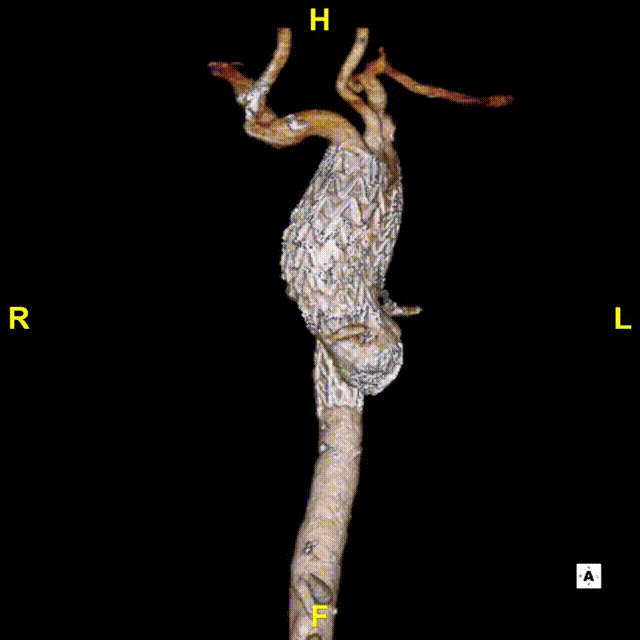

患者出院前进行CTA复查,可见溃疡隔绝完全,弓上分支血管及冠状动脉通畅。

术后3D动态

术后3D重建